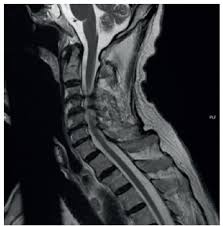

La polineuropatía idiopática aguda, más conocida como síndrome de Guillain-Barré, es una afección neurológica de inicio súbito o subagudo que se caracteriza por una disfunción progresiva del sistema nervioso periférico.…